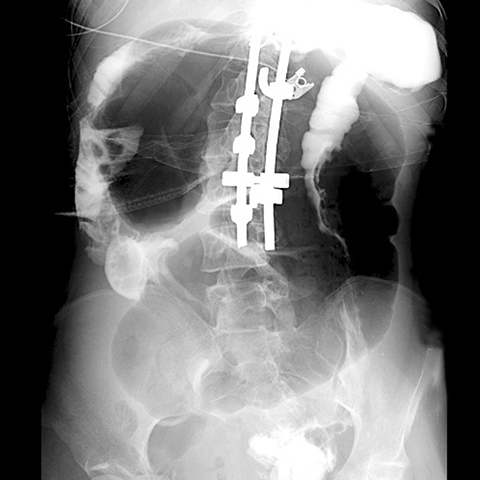

Cecal Volvolus, plain radiograph [3 of 3]